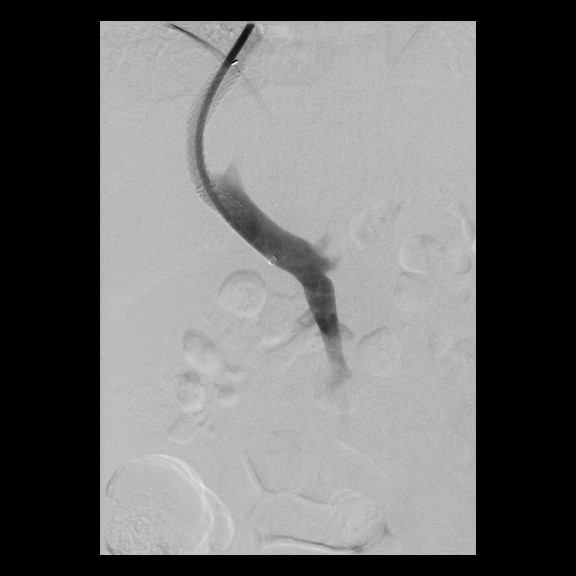

Erfolgreiche Implantation eines transjugulären intrahepatischen portosystemischen Shunts (TIPSS) bei Leberzirrhose und refraktärem Aszites. Transhepatische Punktion der Pfortader unter sonographischer Kontrolle

(Bild 3 von 4)